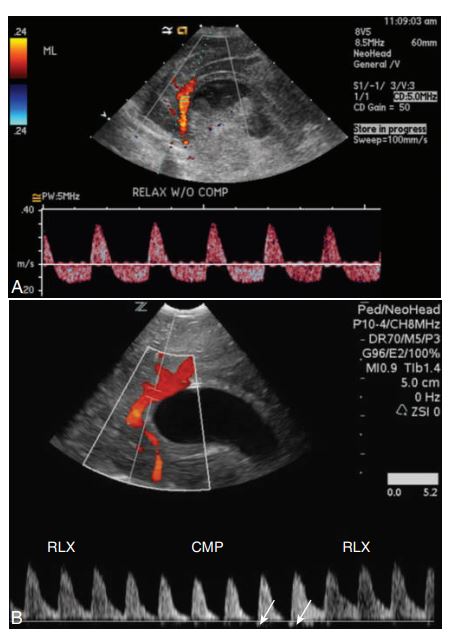

Spectral Doppler of the pericallosal artery in the presence of hydrocephaly to evaluate for intracranial pressure (ICP). (A) Neonate with bilateral grade IV hemorrhage and a diffusely echogenic and swollen brain demonstrates reversal of diastolic flow without compression, indicating elevated ICP.

(B) Premature infant with bilateral periventricular leukomalacia shows an absence of diastolic flow with compression on the anterior fontanel. The small bit of reversal of flow shown with arrows indicates ICP is increasing. CMP, With transducer compression; RLX, with relaxation.

Spectral Doppler to evaluate for increased intracranial pressure.